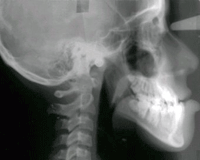

Caso 2: Paciente E. D.

Edad cronológica: 12 años 11 meses................................ Fecha de nacimiento: 6 - 7 - 85

Edad ósea según atlas de Greulich y Pyle:............... QUINCE AÑOS 6 MESES

Maloclusión: Esquelética de Clase III

Tratamiento: Primera etapa: Tto. ortodóncico interceptivo.

Segunda etapa: Cirugía ortognática.

ESTUDIO DE EDAD ÓSEA:

Puede verse una parte del contorno del tubérculo del hueso escafoides.

El hueso sesamoideo puede verse a nivel de la cabeza del 1er. hueso metacarpiano, inmediatamente lateral.

La epífisis del 1er. hueso metacarpiano, se fusionó recientemente con su diáfisis y las epífisis de los otros huesos metacarpianos están comenzando a fusionarse.Se observa cierta fusión en las falanges distales de los dedos.

El desarrollo óseo que se observa en esta toma radiográfica corresponde en los varones a la etapa de la pubertad.